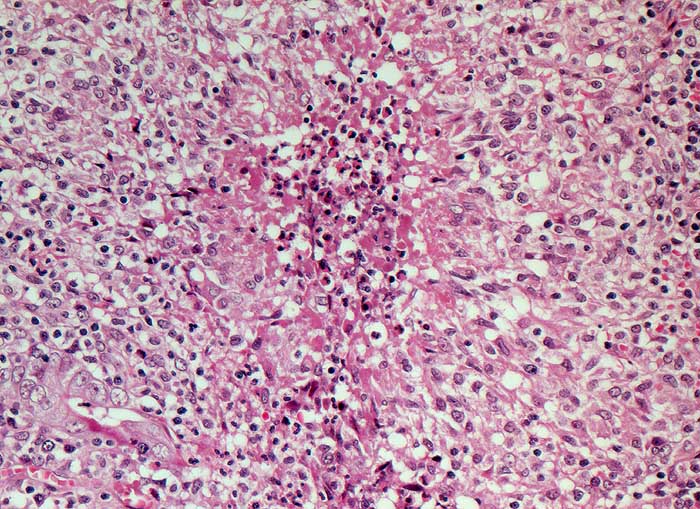

Di dimensioni considerevoli rispetto a quelle di altri artropodi primitivi, questo animale poteva raggiungere i 12 centimetri di lunghezza, anche se la maggior parte degli esemplari rinvenuti era di dimensioni minori. Lo scudo cefalico era corto, ed era seguito da una decina di segmenti corporei (tergiti) che si sovrapponevano l'uno all'altro. La parte posteriore del corpo era costituita da un grosso scudo e da una lunga coda segmentata. Tutte le tergiti erano dotate di una superficie costituita da poligoni irregolari, sconosciuta tra gli altri artropodi di Maotianshan.

Ventralmente erano presenti due occhi posti su peduncoli, e subito accanto vi erano due lunghe antenne provviste di corte setole. Come molti artropodi primitivi, anche questo animale possedeva le classiche appendici biramate, in numero di diciotto paia. Tre di queste erano posizionate sotto la testa, dieci corrispondevano alle tergiti toraciche e cinque erano presenti nello scudo caudale. Le appendici erano costituite da un ramo con funzione deambulatoria (endopodio) dotato di margine interno spinoso, e da un ramo – branchia (esopodio) formato da una struttura a forma di pinna, costituita da una ventina di setole.